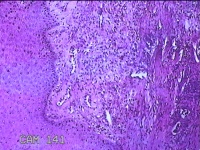

右侧食指远端结节

性别

男

年龄

47岁

临床诊断

皮下结节

一般病史

发现右侧食指3天。

标本名称

大体所见

灰白暗红色带皮肤样结节1.2x0.7x0.3cm一个,表面糜烂,切面灰白粉红色,质中。